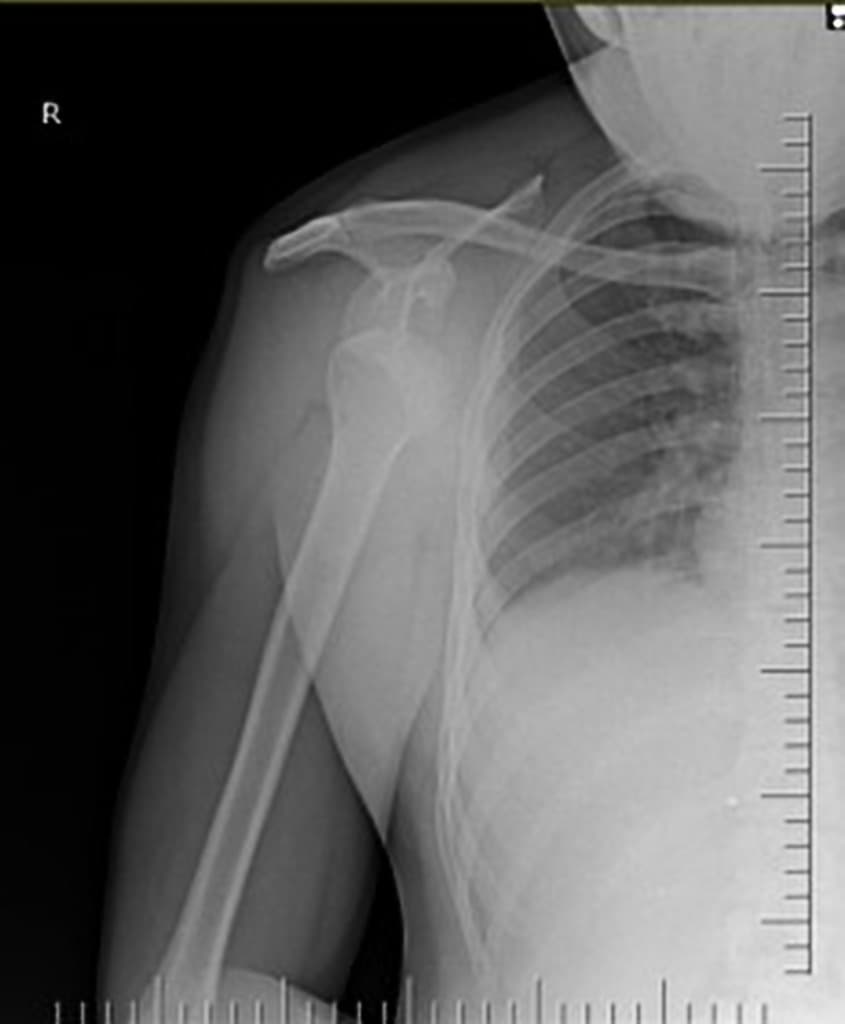

- Không có gãy xương hoặc lệch trục.

- Gai xương sụn tiếp hợp nhỏ ở mặt bên đoạn xa xương quay.

Hình ảnh X-quang và CT đẹp minh họa gai xương sụn tiếp hợp đoạn xa xương quay, do sự đóng không hoàn toàn của đĩa tăng trưởng (physis), đôi khi có thể bắt chước hình ảnh gãy xương.

Gai xương sụn tiếp hợp (epiphyseal spur)

Gai xương sụn tiếp hợp là một dạng biến thể phát triển do sự hợp nhất không hoàn toàn của đĩa tăng trưởng đoạn xa xương quay, thường xuất hiện như một mào xương nhỏ, có viền cốt hóa rõ ở mặt bên đoạn xa xương quay. Tổn thương này thường gặp ở trẻ em và thanh thiếu niên, và thường được phát hiện tình cờ trên hình ảnh học sau chấn thương. Do vị trí và hình dạng, nó có thể bị nhầm với gãy xương do bứt rời cấp tính. Tuy nhiên, các yếu tố như bờ trơn, nối tiếp viền cốt hóa và vị trí đặc trưng giúp phân biệt với gãy xương thực sự. Khi nghi ngờ, việc so sánh với hình ảnh trước đó hoặc chụp cắt lớp vi tính (CT) có thể xác nhận bản chất mạn tính, do phát triển của tổn thương.